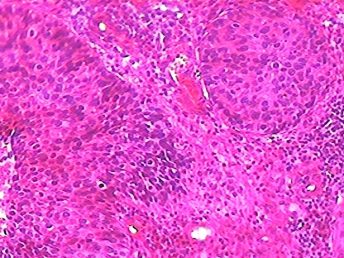

Patología Gastrointestinal

Nuestro staff de patólogos estudia y analiza biopsias para detectar condiciones médicas asociadas a enfermedades inflamatorias, tumores benignos y malignos del tracto gastro intestinal. Incluimos en todos nuestros diagnósticos el proceso técnico y evidencia que prueba la presencia de Helicobacter Pylori.